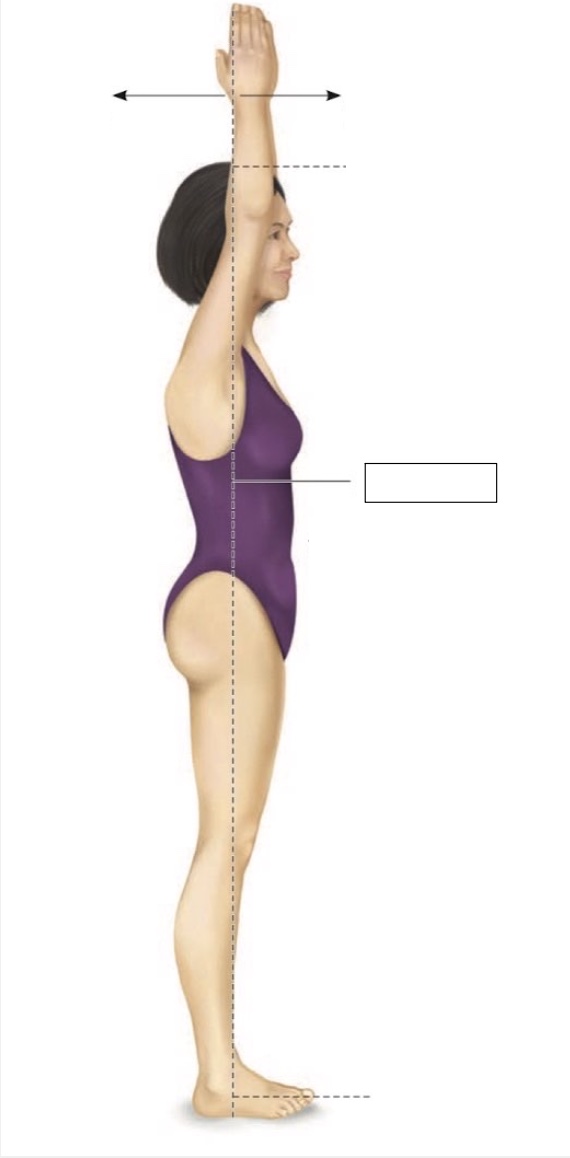

Superior

Midline

Midaxillary

Torso